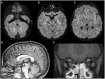

Macrocephaly affects up to 5% of the pediatric population and is defined as an abnormally large head with an occipitofrontal circumference (OFC) >2 standard deviations (SD) above the mean for a given age and sex. Taking into account that about 2-3% of the healthy population has an OFC between 2 and 3 SD, macrocephaly is considered as "clinically relevant" when OFC is above 3 SD. This implies the urgent need for a diagnostic workflow to use in the clinical setting to dissect the several causes of increased OFC, from the benign form of familial macrocephaly and the Benign enlargement of subarachnoid spaces (BESS) to many pathological conditions, including genetic disorders. Moreover, macrocephaly should be differentiated by megalencephaly (MEG), which refers exclusively to brain overgrowth, exceeding twice the SD (3SD-"clinically relevant" megalencephaly). While macrocephaly can be isolated and benign or may be the first indication of an underlying congenital, genetic, or acquired disorder, megalencephaly is most likely due to a genetic cause. Apart from the head size evaluation, a detailed family and personal history, neuroimaging, and a careful clinical evaluation are crucial to reach the correct diagnosis. In this review, we seek to underline the clinical aspects of macrocephaly and megalencephaly, emphasizing the main differential diagnosis with a major focus on common genetic disorders. We thus provide a clinico-radiological algorithm to guide pediatricians in the assessment of children with macrocephaly.